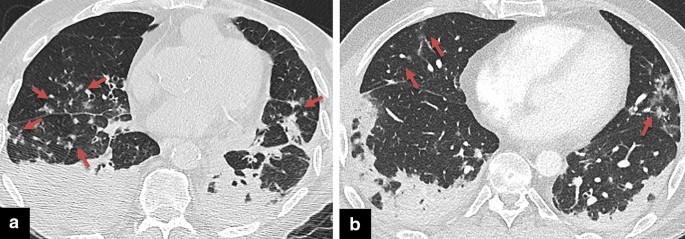

COVID-19 pneumonia may resemble atypical sarcoidosis in some cases with patchy or nodular/mass-like GGOs, consolidations, a crazy-paving pattern, and a reverse halo sign (Fig. 13). Typical findings of sarcoidosis such as mediastinal and/or bilateral hilar lymphadenopathies and perilymphatic nodular opacities with upper lobe predilection do not match those of COVID-19 pneumonia [51, 52]. In sarcoidosis, the consolidation ring of the reverse halo sign may have nodularities due to the granulomatous process [15].

The reverse halo sign in sarcoidosis and COVID-19 pneumonia. a Sarcoidosis presenting with organizing pneumonia pattern, peripheral GGOs, and reverse halo signs (arrows). b Opacities in COVID-19 pneumonia with reverse halo sign in right lower lobe (arrow). Concomitant multifocal opacities are observed